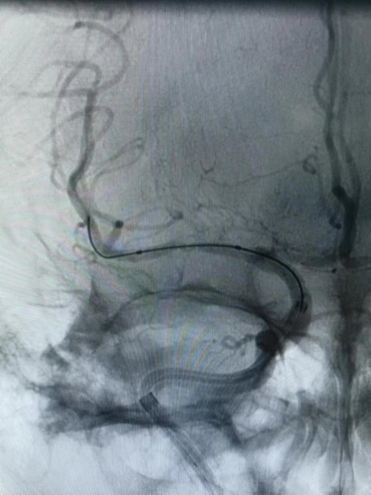

入院影像检查

导丝怎么扩【载药时代 球扩天下】NOVA DES®颅内药物洗脱支架在大脑中动脉重度狭窄的应用二例!_https://www.jmylbn.com_新闻资讯_第3张

MRI+DWI

重要影像结论:右侧放射区、右侧基底节区、左侧额叶近大脑镰处多发急性梗死。

导丝怎么扩【载药时代 球扩天下】NOVA DES®颅内药物洗脱支架在大脑中动脉重度狭窄的应用二例!_https://www.jmylbn.com_新闻资讯_第4张

MRI  T2相

重要影像结论:右侧颈内动脉岩骨段管腔内不清晰,眼动脉段远端管腔较对侧明显缩小。

导丝怎么扩【载药时代 球扩天下】NOVA DES®颅内药物洗脱支架在大脑中动脉重度狭窄的应用二例!_https://www.jmylbn.com_新闻资讯_第5张

导丝怎么扩【载药时代 球扩天下】NOVA DES®颅内药物洗脱支架在大脑中动脉重度狭窄的应用二例!_https://www.jmylbn.com_新闻资讯_第6张

重要影像结论:右侧ICA起始部急性闭塞,前交通动脉、后交通动脉未开放。